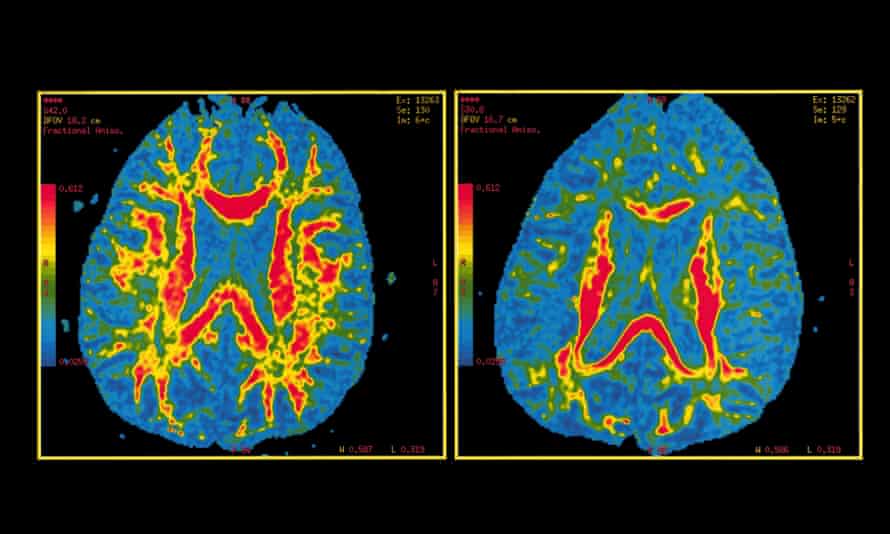

Imgur Com Brain Size Neuroscience Memory Loss